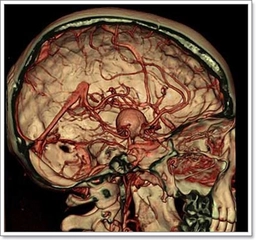

Kireçlenmenin TanısıKireçlenme tanısı genellikle klinik muayene ve görüntüleme yöntemleri ile konulur. Doktor, hastanın tıbbi geçmişini ve belirtilerini değerlendirerek fiziksel bir muayene yapar. Ayrıca, tanıyı doğrulamak için şu görüntüleme yöntemleri kullanılabilir: